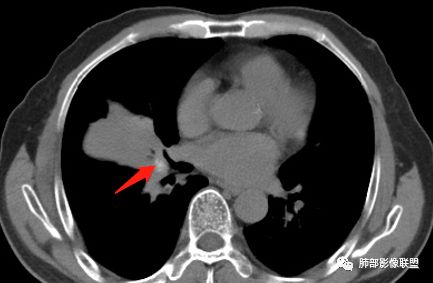

静脉期

吴婧老师和南边老师都对该病例进行了深入分析。从支气管管壁的增厚,支气管狭窄后扩张,支气管粘液栓,病灶形态,到病灶不均匀强化及坏死彻底,到周边病灶及肺组织空气的潴留,加之纵隔内淋巴结肿大伴钙化等等,都支持慢性炎性病灶,尤其是结核。

现在小编来增加一个炎性另一个征象,是我们王兆宇老师原创的----就是墨西哥仙人掌征。

墨西哥仙人掌征---结核        影像上结核灶,粗大的均匀枝干,推测是支气管囊状扩张引起的,在非支气管区,形成圆形坏死囊群;如果这些坏死比较稀薄,又遇到扩张支气管,就会形成粗大的“墨西哥仙人掌”。结核引起的支气管近端炎症纤维化,可以造成支气管阻塞,从而将干酪样坏死物封堵在管腔内。仙人掌主干内部应该是干酪为主,稀薄的,具有流动性,时间久了会出现钙化。

结核坏死与鳞癌鉴别有一点是结核坏死没有方向性,鳞癌有。鳞癌靠近支气管近端部分,血供容易维持,不易坏死,所以坏死靠外侧。而结核干酪样坏死,把一定体积的流动性坏死物,包裹起来,什么形状最省料?坏死物包裹,表面积最省的自然是圆球形,而遇到支气管,坏死物一多,就把支气管撑大了。包裹物是就地取材,扩张的支气管就成了包裹结构。